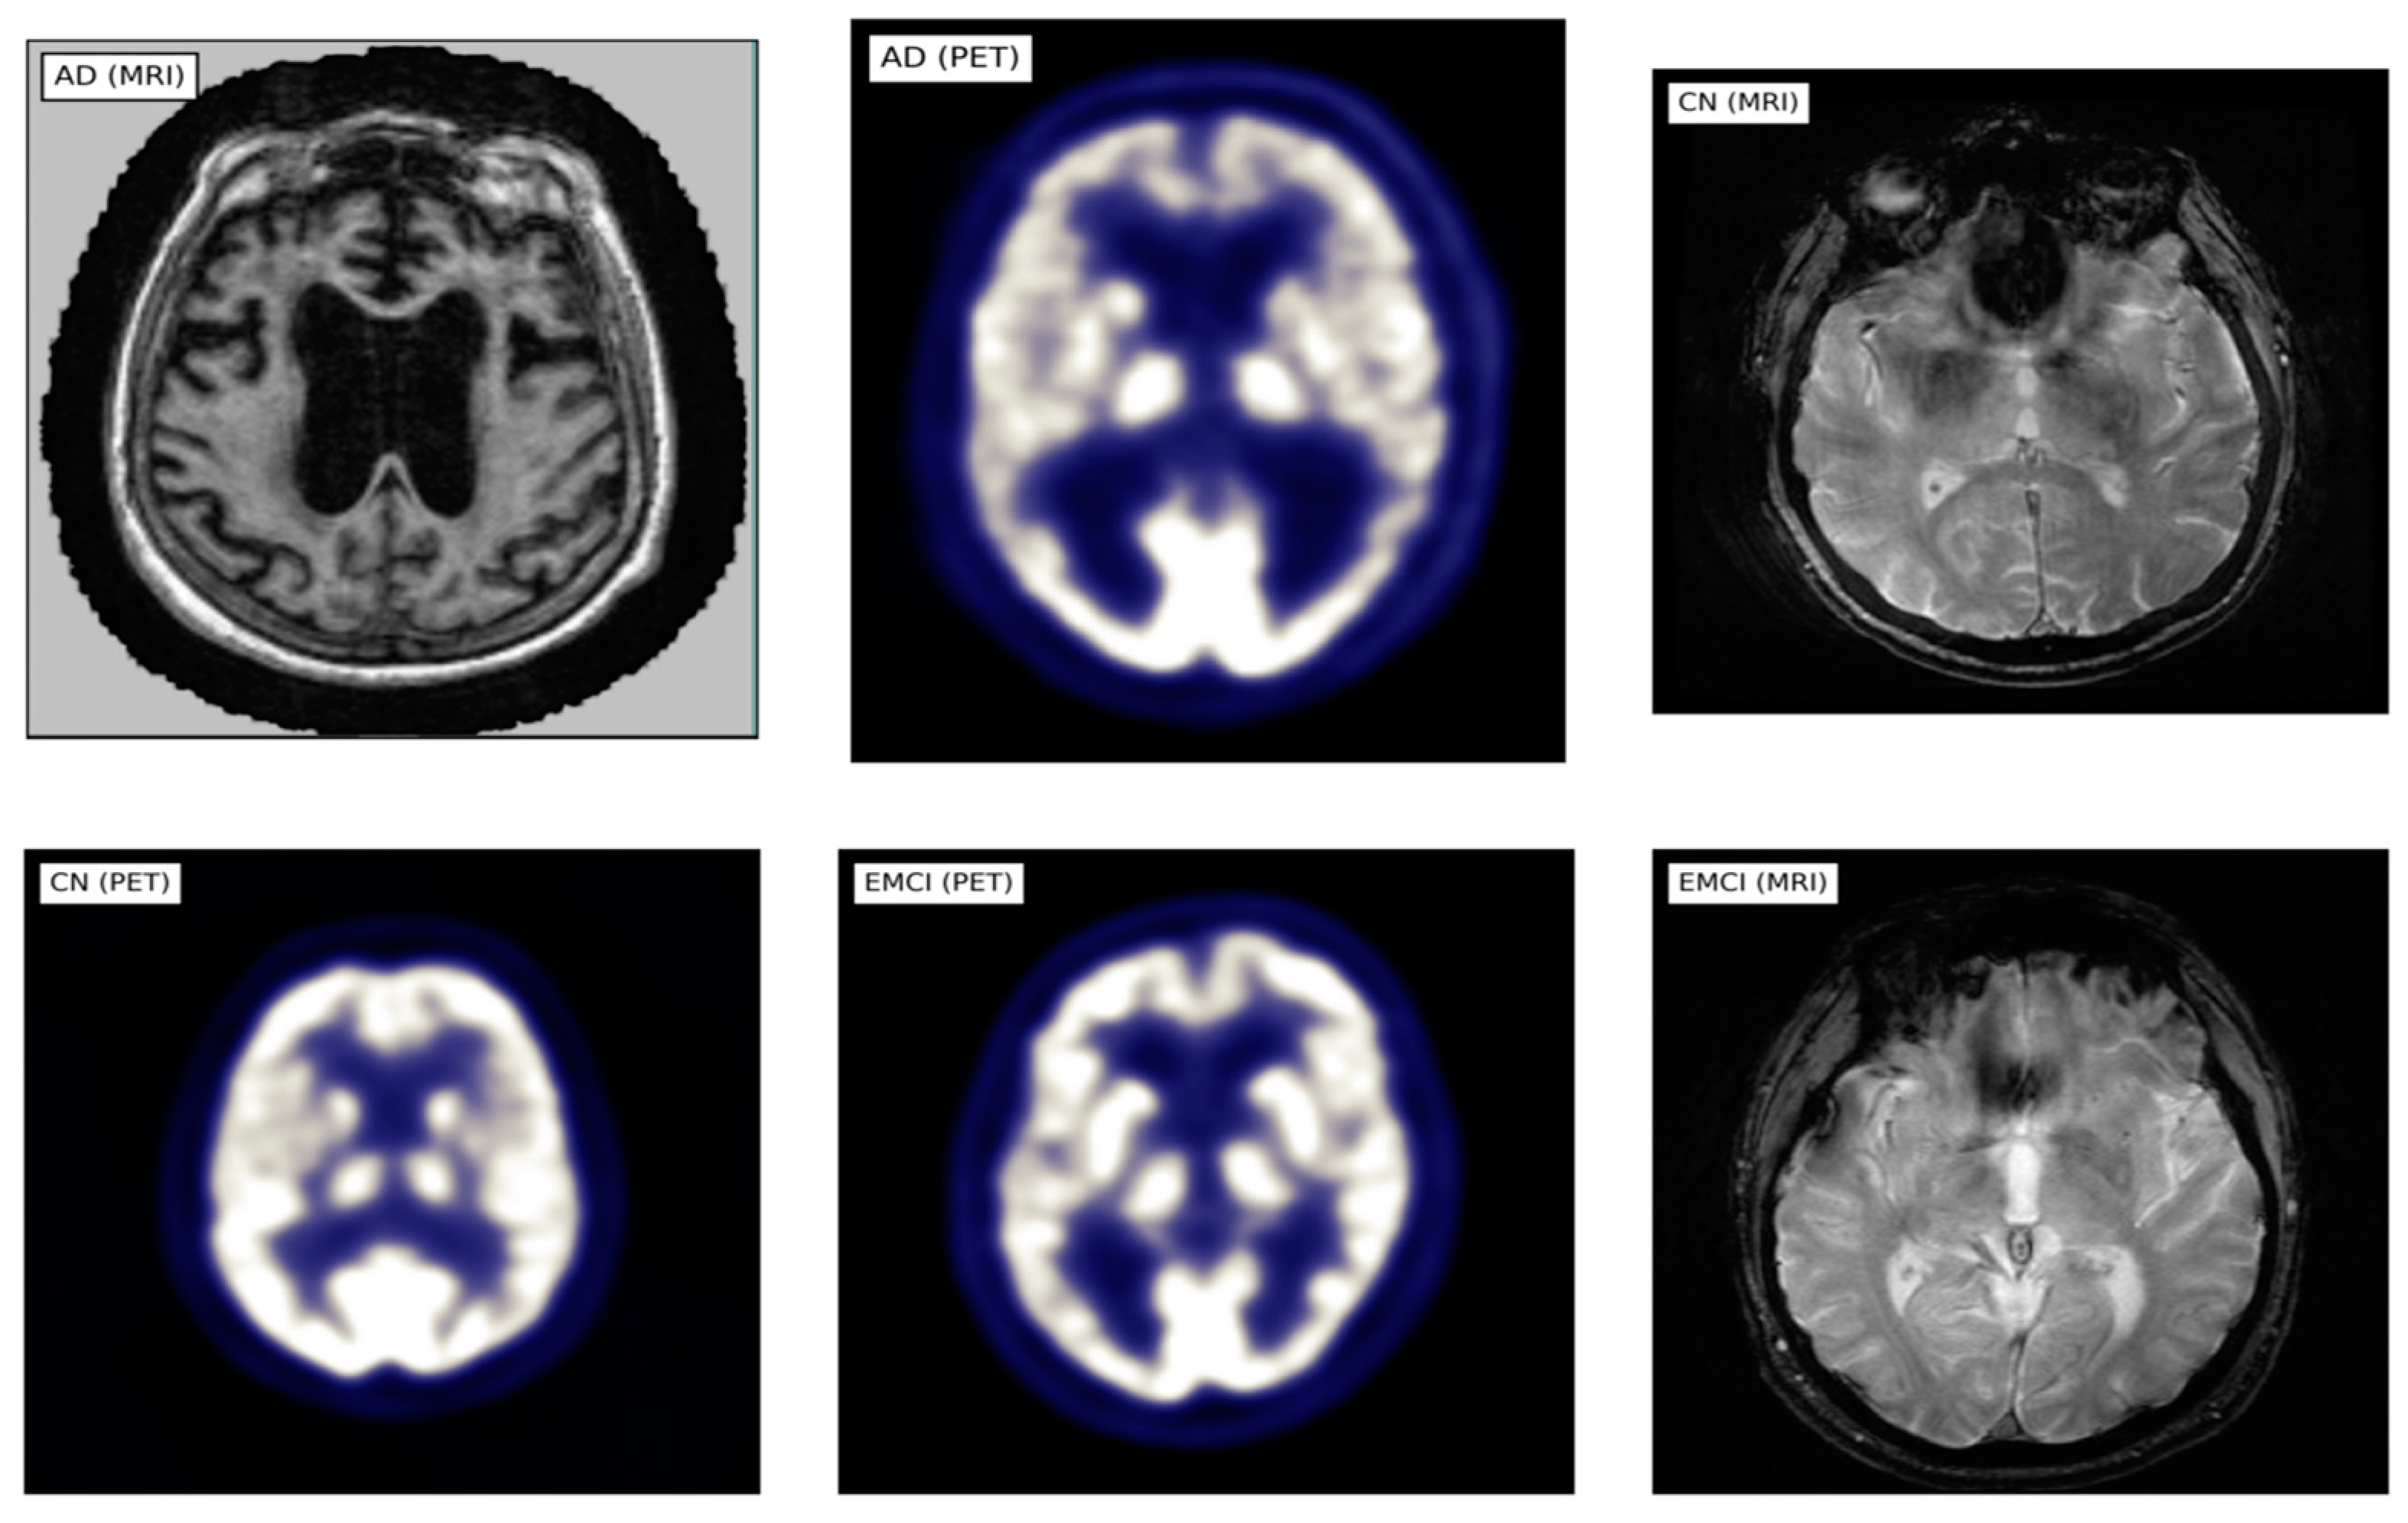

This study utilized MRI and PET images obtained from the official website of Harvard University (http://www.med.harvard.edu/AANLIB/home.html (accessed on 15 September 2023)), the ADNI website (https://adni.loni.usc.edu (accessed on 15 September 2023)), and the OASIS website. The brain images under consideration are categorized into two distinct stages, namely Cognitive Normal (CN) and Alzheimer’s Disease (AD). 50 images of each of the stages are downloaded from each website, making a total of 300 images. PET images are in red, green, and blue (RGB) while MRI images are in black and white. Figure 2, Figure 3 and Figure 4 show sample the datasets used from AANLIB, ADNI, and OASIS database, respectively.

Figure 3.

Sample Images from the ADNI database.